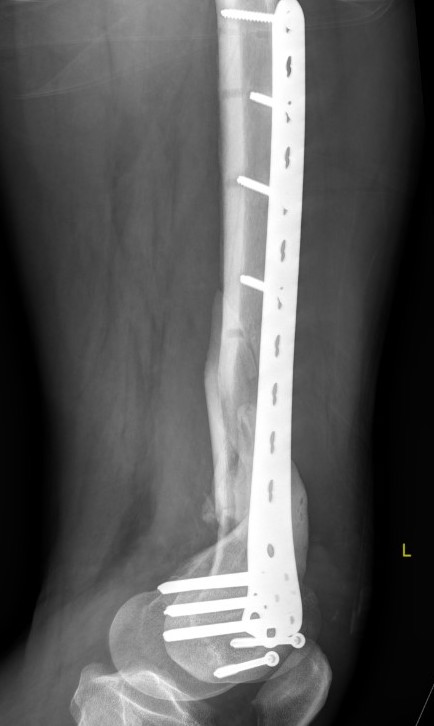

Xray

Options

Lateral plate

Retrograde IM nail